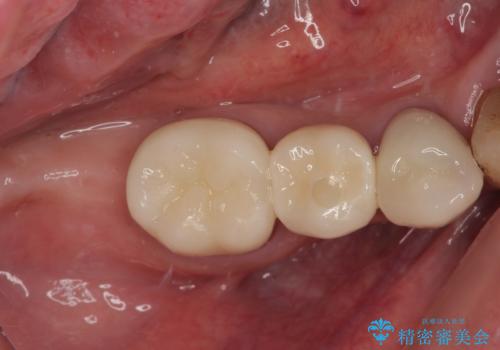

奥歯がしみる オールセラミッククラウンによる奥歯のむし歯治療